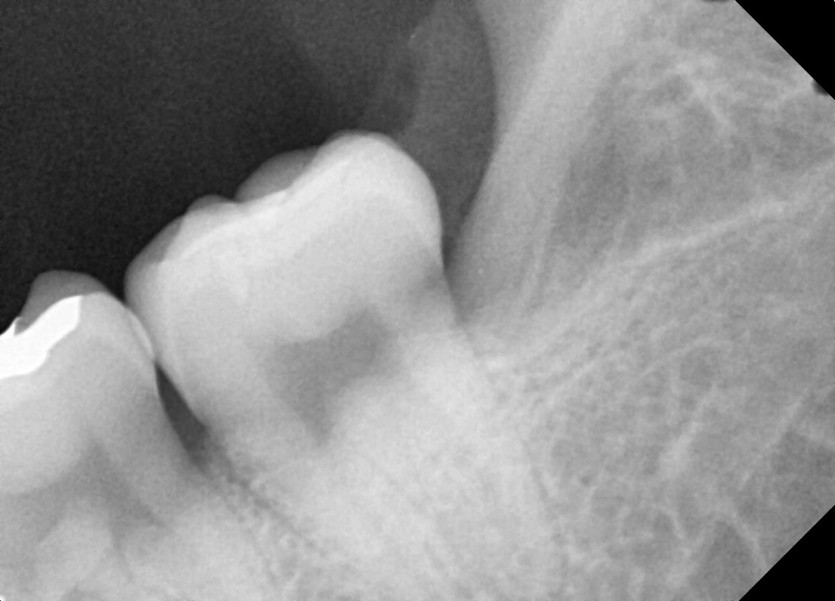

#28,38 사랑니 발치

구강 외과 전문의가 당일 발치했습니다.